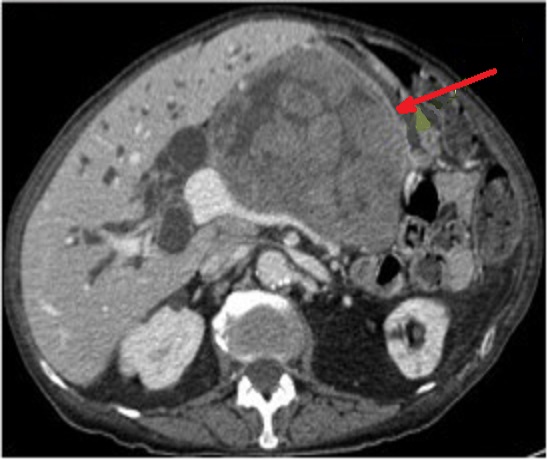

Image

coupe axiale . |

|

Aspect lesionel TDM une masse a hypodense

, homogene mal limitee situe du corps pancreas(

fleche rouge . Rehaussement legere du tumeur apres

injection de contrast intraveineuse . Image

radiologique TDM plus contrast intraveineuse , coupe

axiale . |